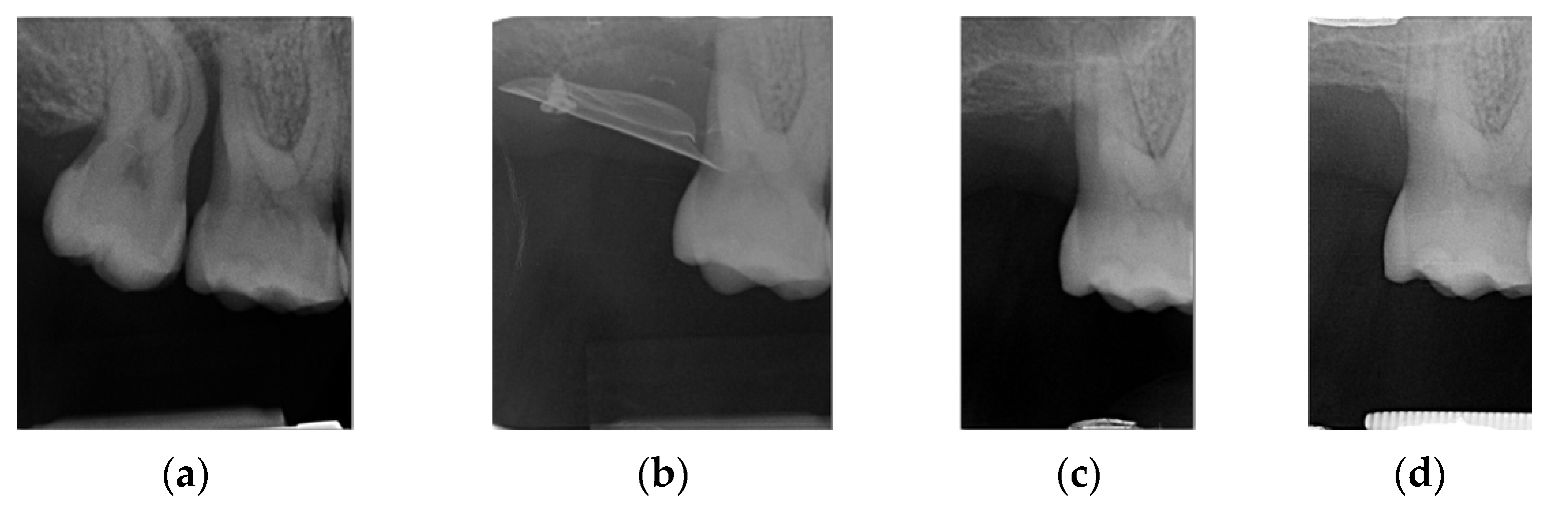

This 45-year-old male patient was scheduled for prosthetic rehabilitation of the posterior maxillary area. After a radiological check, it was decided to proceed with a lateral sinus lift approach (Figure 1a,b).

(a,b): First quadrant clinical aspect and TAC X-ray image.

The pre-implant CT showed (Figure 4) the new bone volume obtained with the procedure, which was sufficient to allow the implant insertion.

Foil radiographic checks: in evidence the shape of the foil.